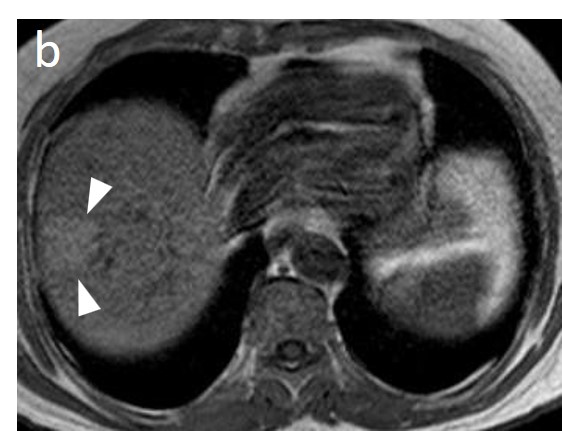

As mentioned before, the radiological hallmark that enables a confident non-histological diagnosis of HCC is the combination of hypervascularity on the arterial phase and hypoperfusion on the portal phase; as with CT, this “wash-in/wash-out” pattern is indispensable on MRI as well. According to the LI-RADS criteria, no lesion without hyperenhancement on the arterial phase can be definitely characterized as HCC; hyperenhancement has to be “non-rim”, i.e., not predominantly peripheral (in order to differentiate from metastases or cholangiocarcinoma) [51]. However, up to 40% of HCCs show no hypervascularity on the arterial phase, and these mainly represent early or poorly-differentiated HCCs [131,132]. Moreover, 40–60% of small HCCs lack wash-out during the portal phase [133,134] (Figure 10). Additional major and ancillary features are employed to help characterize the lesion and assign a LI-RADS category to it.

Figure 10. Evolution of a cirrhotic nodule into HCC. No suspicious lesions are identified on the T2 (a) and DWI (b) sequence of this 66-year-old man with cirrhosis due to hepatitis B infection. On the follow-up scan, performed 3 months later, increased T2 signal (c) is now observed in a nodule in segment V, which is associated with diffusion restriction (arrow) (d). After contrast administration, arterial enhancements (e) without delayed wash-out (f) are seen; absence of wash-out is frequent in early HCCs.